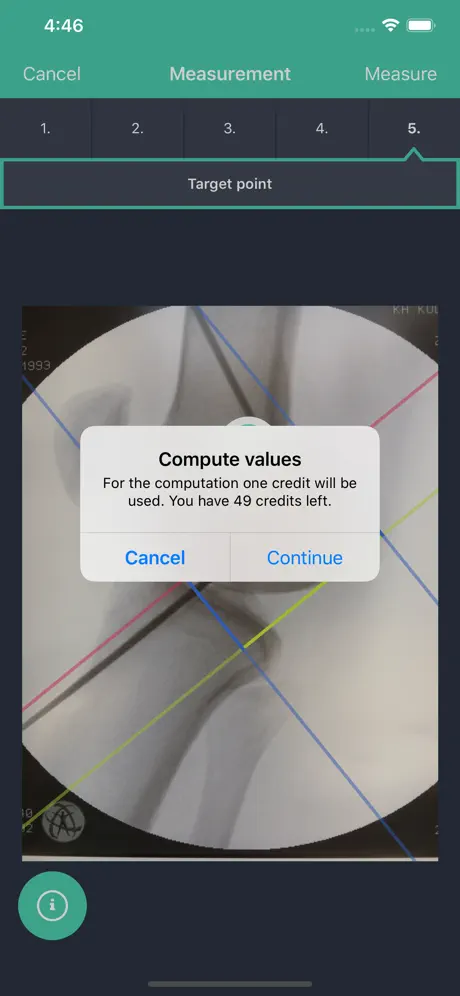

By means of supporting lines that you can overlay virtually over the X-ray photograph in the app, the app can calculate the relative distance of the target point for the k-wire for a femoral or tibial surgery.

In the medical literature, femoral measurement of a radiographic image is known as quadrant method by Bernard and Hertel. It may help knee surgeons identify the ideal position for bone tunnel placement during ACL reconstruction.

During the operative procedure, place a guide wire (or the tip of an microfracure awl) into the center of the femoral insertion area using your standard operative set up. Alternatively, you may may advance the k-wire in the center of the projected bone tunnel forward penetrating the skin on the lateral side of the femur so the end of the wire is flush with the femoral cortex of the insertion.

The app will display the relative ratio of your target point in reference to the outlines of the bone of the femoral condyles. The measurement values relate to the relative distance of the target point of the most posterior and proximal border of the condyles.

Tibia measurement of a radiographic image has been described by Stäubli und Rauschning. It may help knee surgeons identify the ideal position of the tibial bone tunnel during ACL reconstruction.

Place a guide pin into the center of the projected tibial bone tunnel using a drill guide in a normal fashion. The guide pin may intrude the joint beyond the cortical edge of the ACL footprint.

This app will display the relative distance (in percent) of the entry point of the guide wire into the joint in relation to the total anterior posterior (AP) distance of the proximal tibia (100 %).